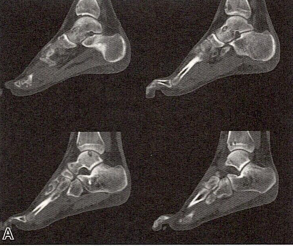

患者男,16岁。右踝关节疼痛不适。影像学检查显示右胫骨下端和足骨多灶性病变,临床和影像学诊断多骨性朗格汉斯细胞组织细胞增生症,行活检,镜下形态如图所示。